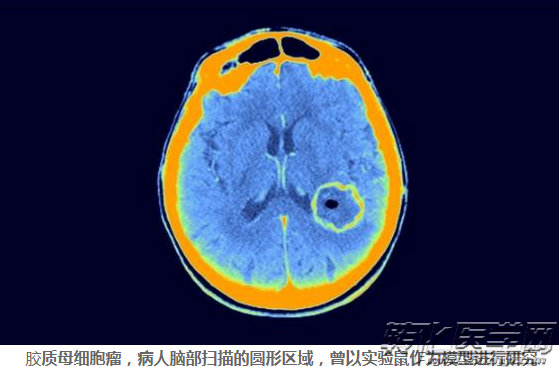

分析表明,植入小鼠的人类肿瘤细胞会以人体不常见的方式发生变异。例如,人类胶质母细胞瘤倾向于获得7号染色体的额外拷贝,但PDX小鼠模型则会随着时间的推移丢失这些额外的拷贝。